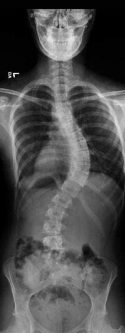

Scoliosis

Abnormal or exaggerated lateral curvature of the spine

Most common in 10-14 y/o, more in females

Severe scoliosis cases may complicate ____ function and require surgery.

Cardiac and respiratory

Treatment for scoliosis includes ____ which can be adjusted as the child grows.

Expandable, permanent correction rods